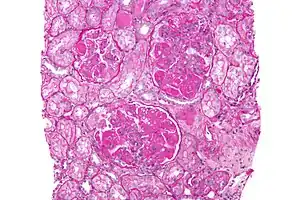

Class IV disease (diffuse proliferative nephritis) is both the most severe, and the most common subtype. More than 50% of glomeruli are involved. Lesions can be segmental or global, and active or chronic, with endocapillary or extracapillary proliferative lesions. Under electron microscopy, subendothelial deposits are noted, and some mesangial changes may be present. Clinically, haematuria and proteinuria are present, frequently with nephrotic syndrome, hypertension, hypocomplementemia, elevated anti-dsDNA titres and elevated serum creatinine.[14]